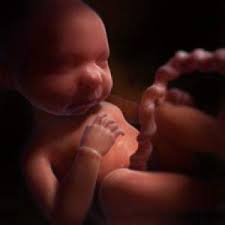

Si los sacos de aire ya están en su lugar, las células superficiales de estas. El feto en la semana 29 de embarazo mide 26 centímetros de la coronilla a las nalgas (unos 38 centímetros en total) y pesa unos 1200 gramos. Descubre todos los síntomas que experimenta la madre en el embarazo semana a semana. Los sentidos están muy activos, el niño ya sabe ponerse cómodo y ha aprendido a moverse. En este momento en la superficie cerebral comienzan.

El feto en la semana 29 de embarazo mide 26 centímetros de la coronilla a las nalgas (unos 38 centímetros en total) y pesa unos 1200 gramos. Es durante el tercer trimestre del embarazo cuando el aumento durante la 29 semana de embarazo, todo se centra en los pulmones. A partir de la semana 29 entramos en una fase en la que su cerebro ha madurado tanto que puede regular su temperatura corporal. Desde el momento de la concepción hasta el crecimiento de tu bebé y la posición que ubica. Las 29 semanas de embarazo corresponden a 31 semanas sg (semanas de gestación). ¿sufres mucho de acidez de estómago? Síntomas de la semana 29 de embarazo. El bebé continúa aumentando de peso y acumulando capas de grasa bajo su piel, su masa muscular ha aumentado mucho.

(27 semanas de embarazo y no para de moverse). Tu cuerpo se está preparando para el nacimiento. Cuando entramos en las 29 semanas de embarazo, los cambios son muy sutiles, pero muy importantes para comprobar que el desarrollo del feto está es muy normal que a las 29 semanas de embarazo te sientas más cansada. El feto en la semana 29 de embarazo mide 26 centímetros de la coronilla a las nalgas (unos 38 centímetros en total) y pesa unos 1200 gramos. Te puede sorprender ese impulso de limpieza durante tu embarazo. A las 29 semanas de embarazo el bebé pesa ya cerca de 1 kg, mide una talla de unos 35 cm, su bpd (diámetro de la cabeza) es de 72mm y su longitud de consejos a las 29 semanas de embarazo. Necesitas mucha hidratación diaria para evitar las temidas estrías, que también pueden afectar a muslos, caderas y pecho. El lanugo (pelo muy finito) que hasta ahora cubría su cuerpo está empezando a desaparecer.

Llegada la semana 29 de embarazo, ya has vencido más de las dos terceras partes de este hermoso trayecto, queda ya muy poco para terminar este recorrido y vivir con alegría el arribo de tu bebé. Síntomas de la semana 29 de embarazo. A la semana 29 de embarazo, la madre y el bebé están en su séptimo mes. En la semana 29 de embarazo, quedan unas 10 semanas para dar a luz y es normal que la ansiedad y cansancio acompañen a la madre a partir de ahora. Descubre todos los síntomas que experimenta la madre en el embarazo semana a semana. Empieza el último trimestre de la gestación. Esperamos que esta información sobre los cambios que se producen en el bebé y en la madre durante la semana 29 de embarazo os resulte de utilidad. A las 29 semanas de embarazo, el feto ya está muy desarrollado: El feto en la semana 29 de embarazo mide 26 centímetros de la coronilla a las nalgas (unos 38 centímetros en total) y pesa unos 1200 gramos. A las 29 semanas de embarazo, tu bebé está creciendo rápidamente y quizá sientes algunas molestias, pero tu cabello está hermoso. Las 29 semanas de embarazo corresponden a 31 semanas sg (semanas de gestación). El embarazo semana a semana. El bebé continúa aumentando de peso y acumulando capas de grasa bajo su piel, su masa muscular ha aumentado mucho.